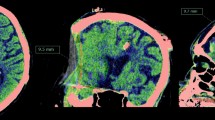

Average and standard deviation values of strain are reported in Table 3, alongside the corresponding inter-subject variability. Figures 4 and 5 show the distribution of the hydrostatic and the deviatoric strains, respectively. Strain maps show elongation in frontal regions and confirm the negligible deformation in posterior regions as previously noticed. Local variability of deformation can be seen, as well as some structures (such as ventricles) and anatomical boundaries (such as the falx cerebri and the tentorium cerebelli). The polar plots in Fig. 6 show the diagonal components of the strain tensor for different lobes also decomposed in its hydrostatic and deviatoric components. Deformation along P–A direction occurred as both volume preserving (\(0.52\pm 1.02\) %) and volume change (\(0.44\pm 0.64\) %) expansion in the frontal lobe. However, deformation occurred predominantly as shape change in more posterior regions (\(-0.48\pm 1.14\) %), with a small volumetric compression (\(-0.25\pm 0.76\) %).

Distribution of the hydrostatic component at two axial (a and b) and two sagittal (c and d) slices. As reference, three ROI (Vent, STN, BStem) are delineated. Dashed coloured lines represent the position of the other slices. In particular, slice a was positioned at the level of the anterior and posterior horns of the lateral ventricles, whereas slice c was positioned at the level of the falx cerebri.